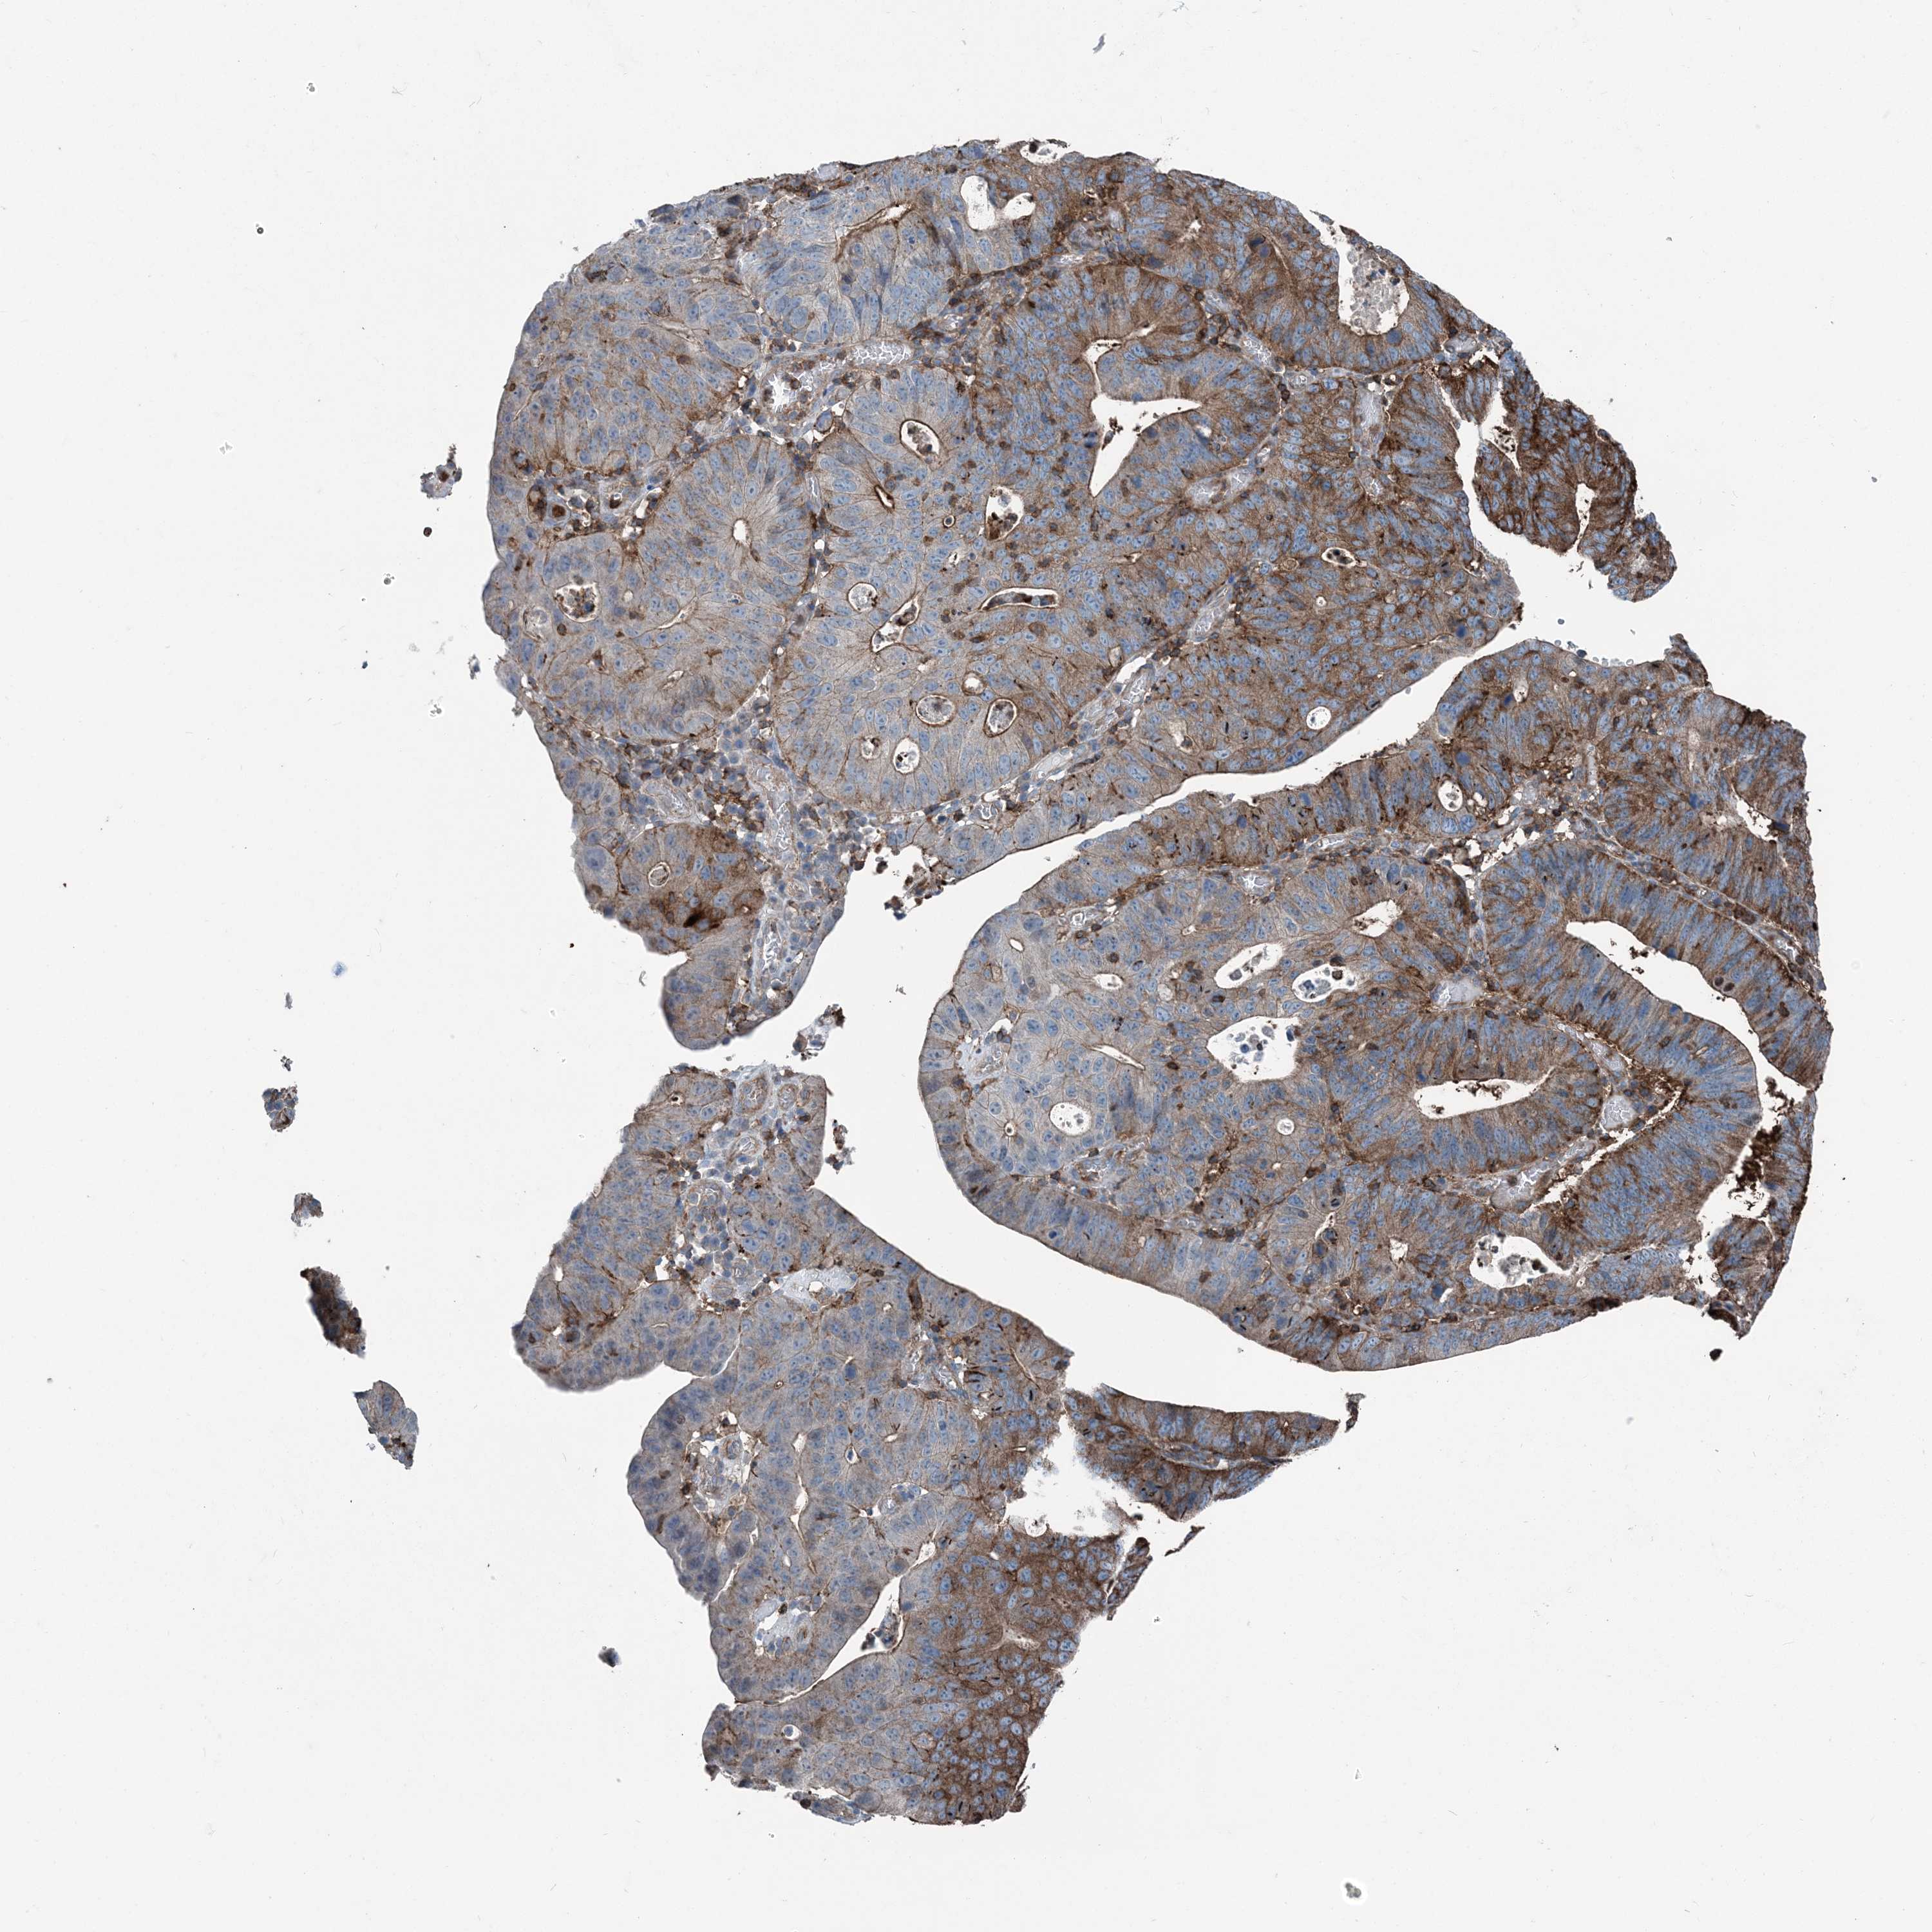

STOMACH CANCER - Protein expressioni

A mouse-over function shows sample information and annotation data. Click on an image to view it in a full screen mode. Samples can be filtered based on level of antibody staining by selecting one or several of the following categories: high, medium, low and not detected. The assay and annotation is described here.

Note that samples used for immunohistochemistry by the Human Protein Atlas do not correspond to samples in the TCGA dataset.

Antibody stainingi

Antibody staining in the annotated cell types in the current human tissue is reported as not detected, low, medium, or high, based on conventional immunohistochemistry profiling in selected tissues. This score is based on the combination of the staining intensity and fraction of stained cells.

Each image is clickable and will lead to virtual microscopy that enables deeper exploration of all samples and also displays staining intensity scores, fraction scores and subcellular localization as well as patient and tissue information for each sample.

Antibody HPA053761

Antibody CAB033687

Antibody CAB037077

Staining

High

Medium

Low

Not detected

Intensity

Strong

Moderate

Weak

Negative

Quantity

>75%

75%-25%

<25%

None

Location

Nuclear

Cytoplasmic/membranous

Cytoplasmic/membranous,nuclear

Adenocarcinoma, NOS